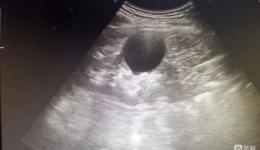

• 【龙中医技术】高精准,超微创!我院超声科成功开展“超声引导下肾囊肿硬化治疗术”!

【龙中医技术】高精准,超微创!我院超声科成功开展“超声引导下肾囊肿硬化...

7月14日,龙泉驿区中医医院超声科成功实施首例肾囊肿硬化治疗。患者男,57岁,因左侧膝关节滑膜炎入院做常规彩超检查,发现大小约4.5cmx5.0cm的右肾囊肿,肾实质受压,囊肿无分隔,初步考虑为单纯性囊肿。术前囊肿大小超声科介入医生周晓霞与患者及...